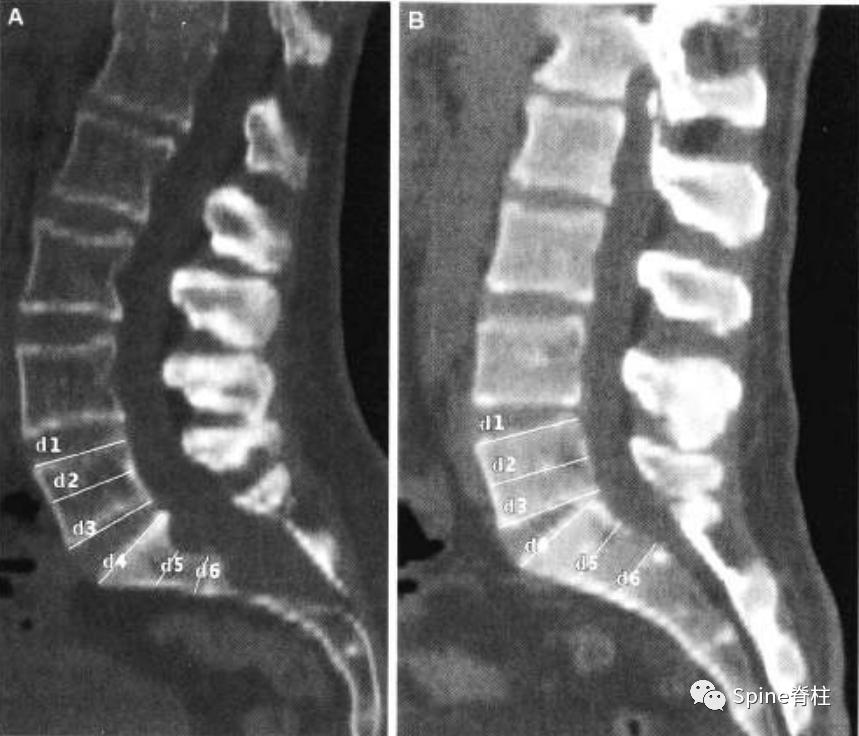

扇形缺损 (scalloping) 的测量。图a为马凡综合征伴硬膜扩张患者的CT正中矢状位重建。扇形缺损定义为椎体上下终板处宽度的平均值减去椎体中央处的宽度。对于这位患者来说,L5的扇形缺损值 (scalloping value) =[(d1+d3)/2]-d2=2.3mm;S1扇形缺损值=[(d4+d6)/2]-d5=4.2mm。图b是马凡综合征不伴硬膜扩张患者的CT正中矢状位重建。L5的扇形缺损值为1.6mm,S1扇形缺损值为0.4mm。